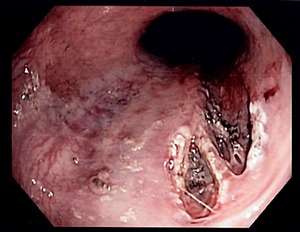

| Mallory–Weiss tear affecting the esophageal side of the gastroesophageal junction | |

Mallory–Weiss syndrome or gastro-esophageal laceration syndrome refers to bleeding from a laceration in the mucosa at the junction of the stomach and esophagus. This is usually caused by severe vomiting because of alcoholism or bulimia,[1] but can be caused by any conditions which causes violent vomiting and retching such as food poisoning. The syndrome presents with painful hematemesis. The laceration is sometimes referred to as a Mallory-Weiss tear.